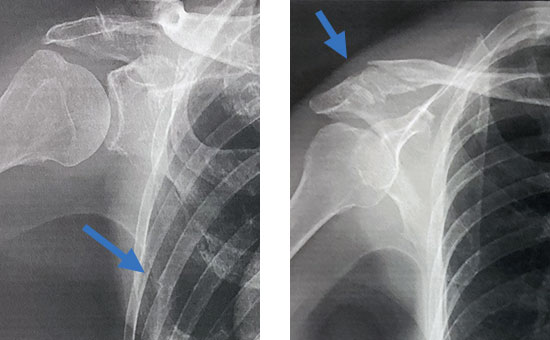

【医学部の名誉大学教授の骨折の写真】

2週間の独活寄生丸で肋骨は癒合し、鎖骨も仮骨してきている。独活丸の骨の融合に必要な量は1日10gだ。一般に骨折が治るのには4-6週間かかるが2週間でほぼ化骨している。